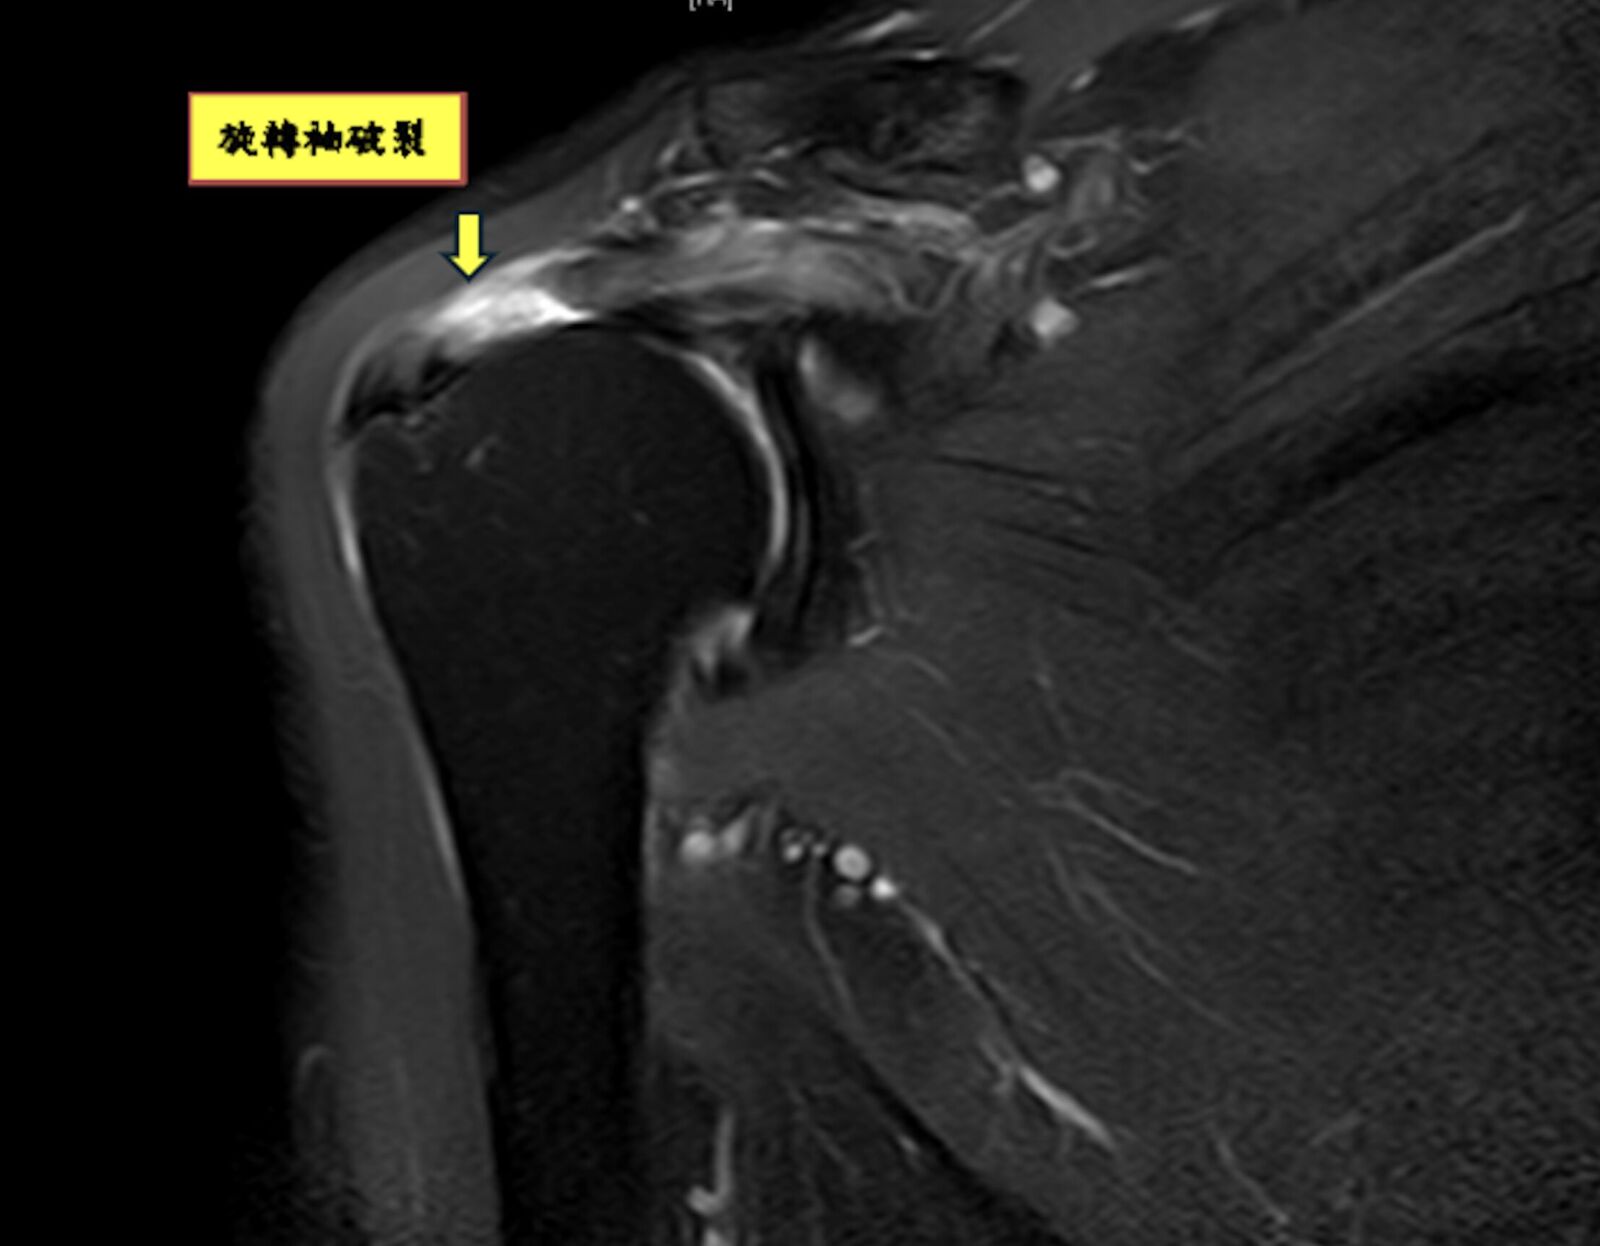

陳昱彰說,常見原因包括:跌倒、車禍、搬重物、長期運動過度使用,或年長者因肌腱退化脆弱,導致旋轉袖破裂。起初常被認為是肌腱拉傷或是五十肩,但許久不癒,建議應先由骨科醫師進行正確診斷與治療,診斷上除了理學檢查、X光、超音波,也常用核磁共振(MRI)來確認破裂程度與型態,作為手術規劃。